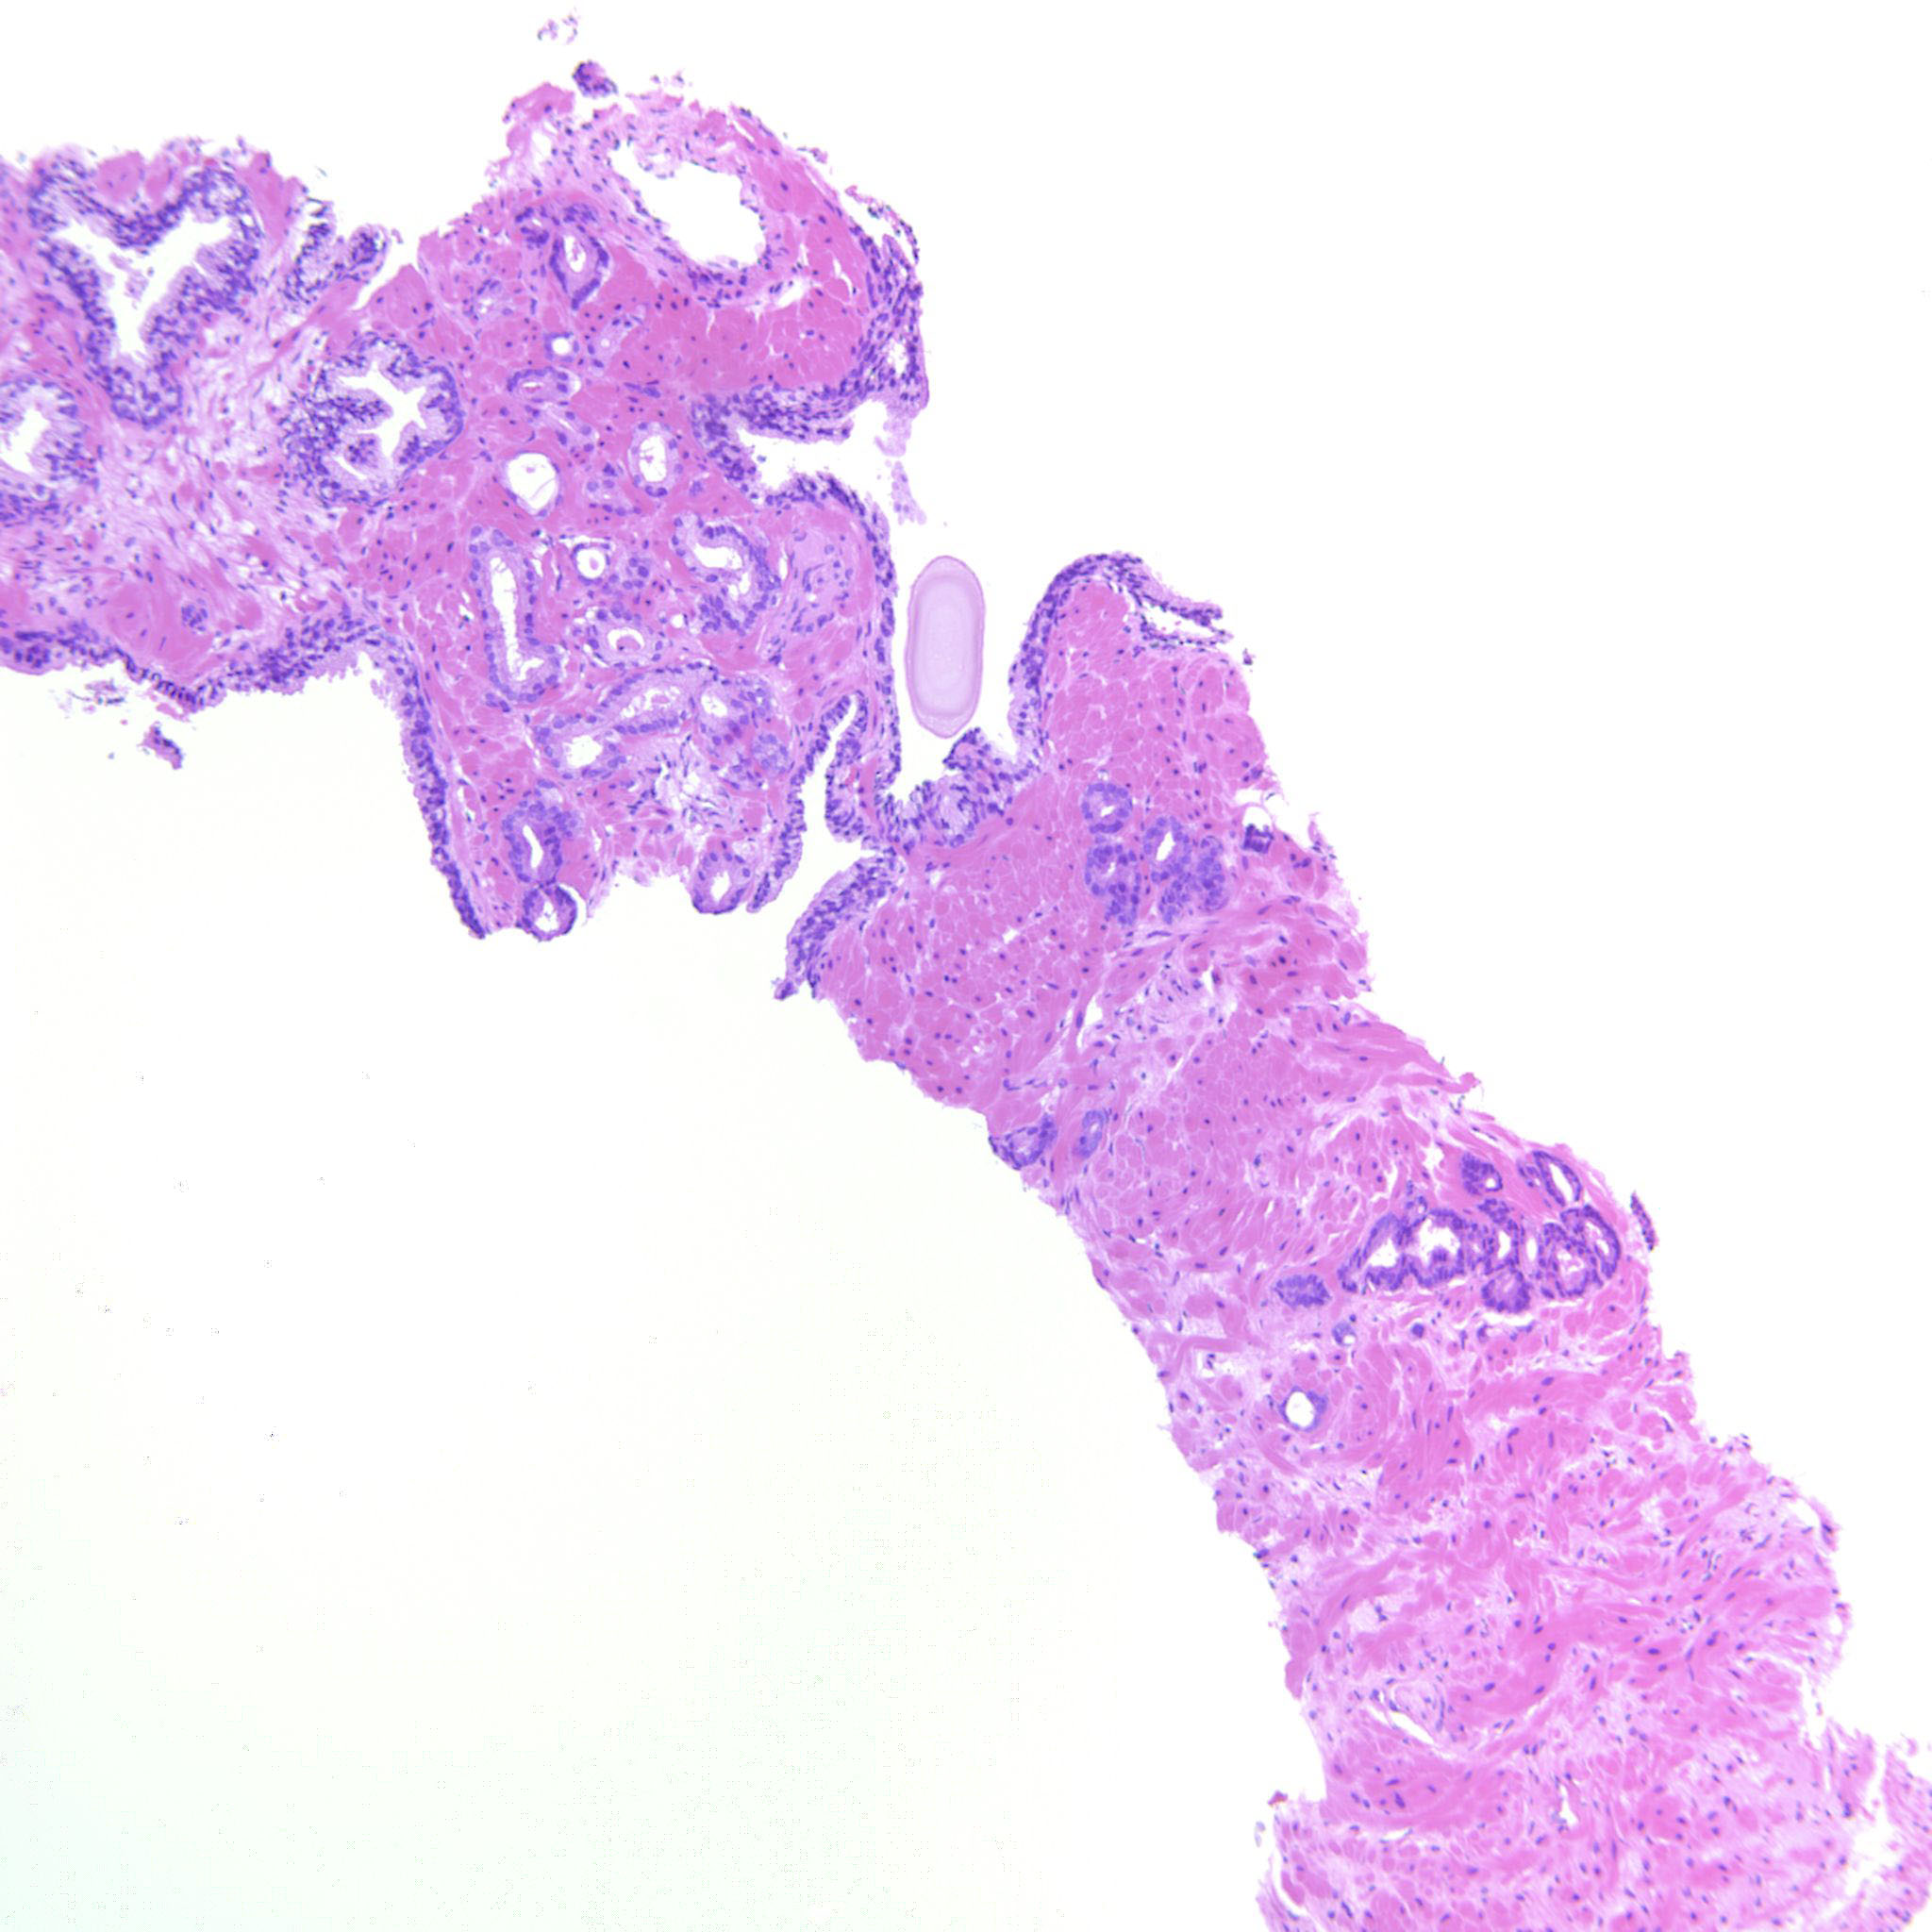

Consensus grade: GS 3+3=6 (ISUP 1)

Case description (by case creator):

A couple of groups of well-formed glands with a few structures that most likely are tangential cuts.